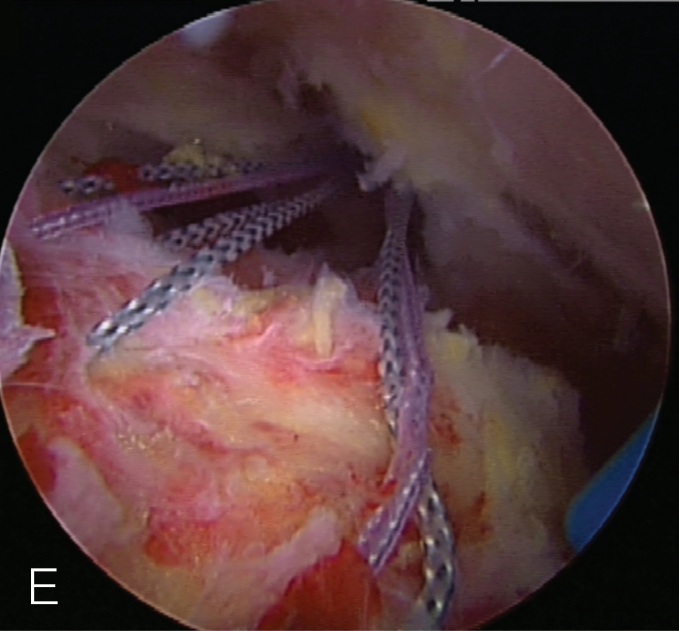

肩袖部分撕裂的修复